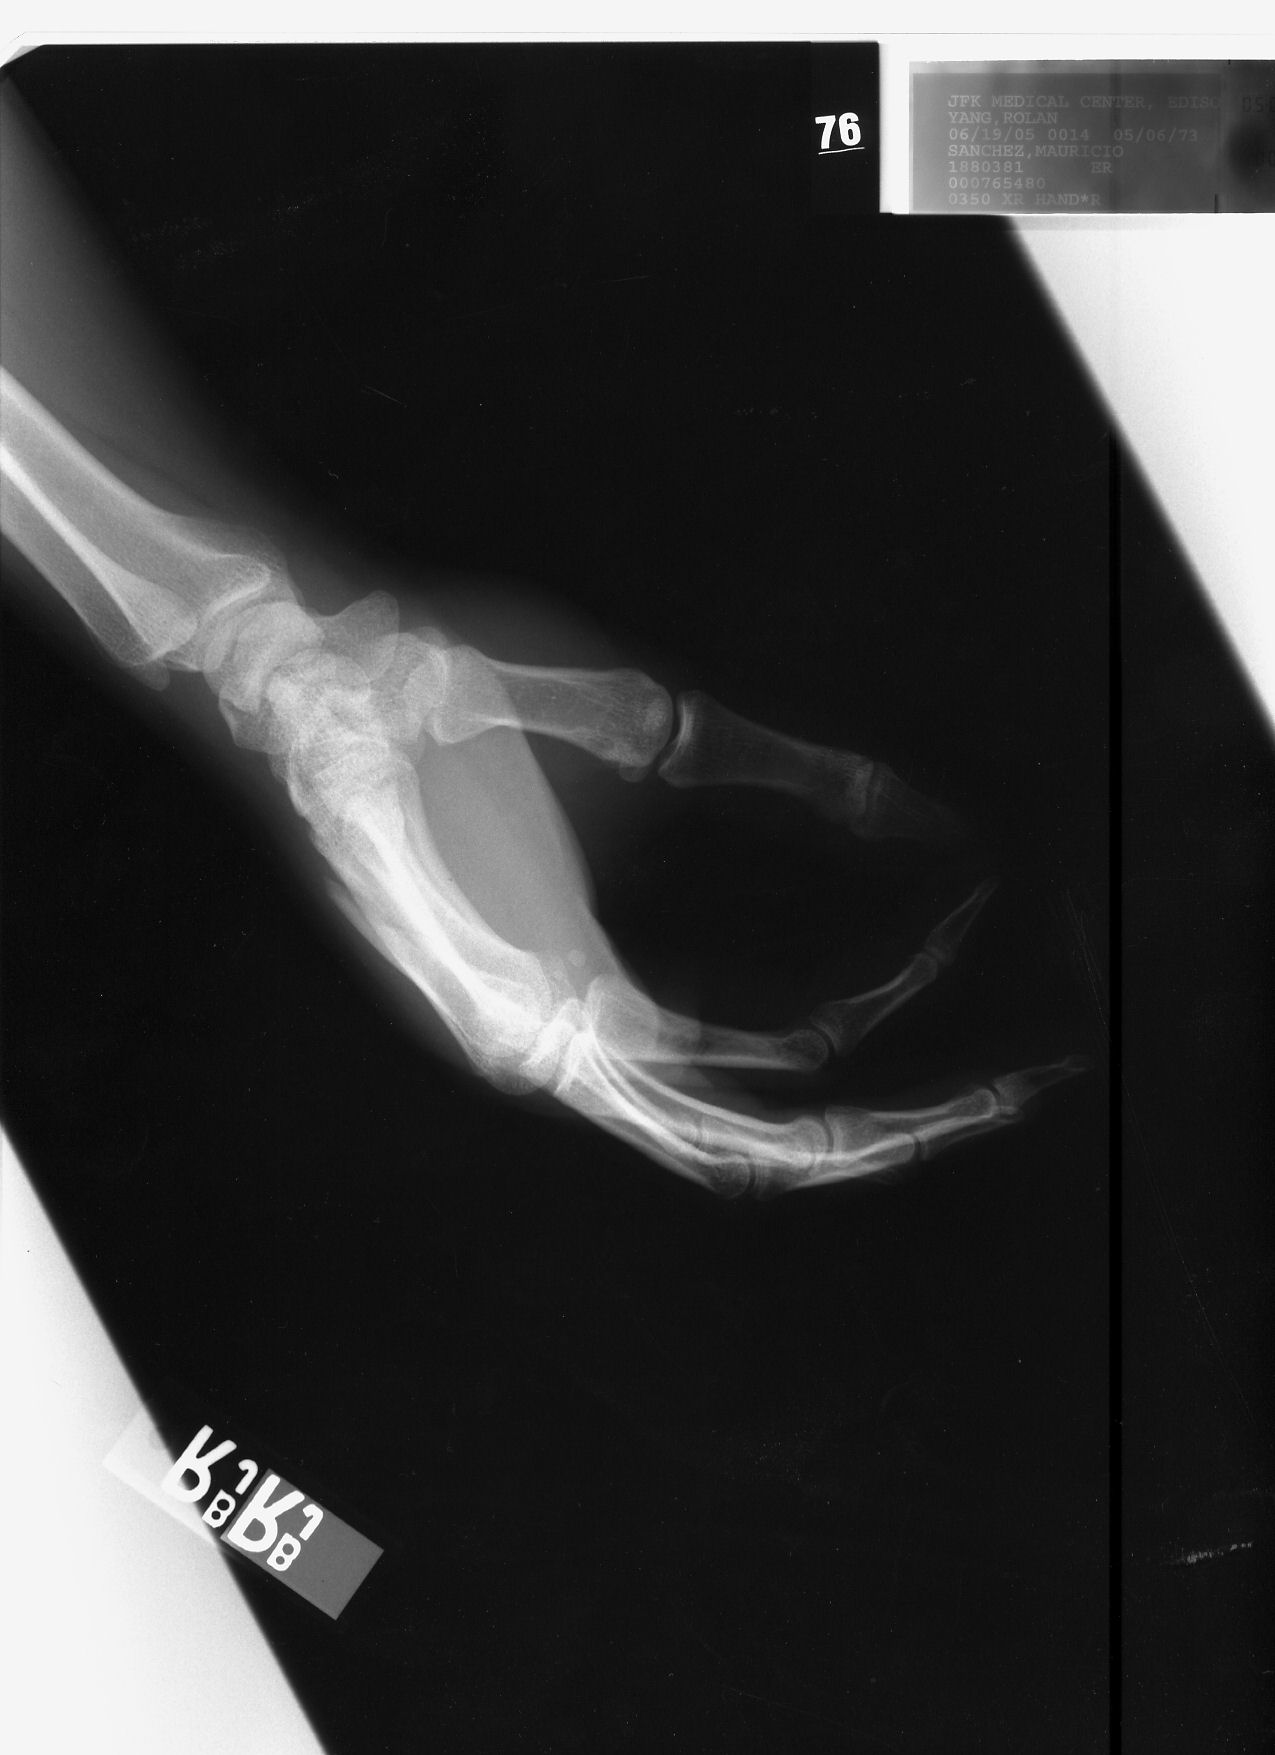

Longitudal fracture fourth metacarpal right hand

6/19/2005 Bone can be seen extending out above the wrist